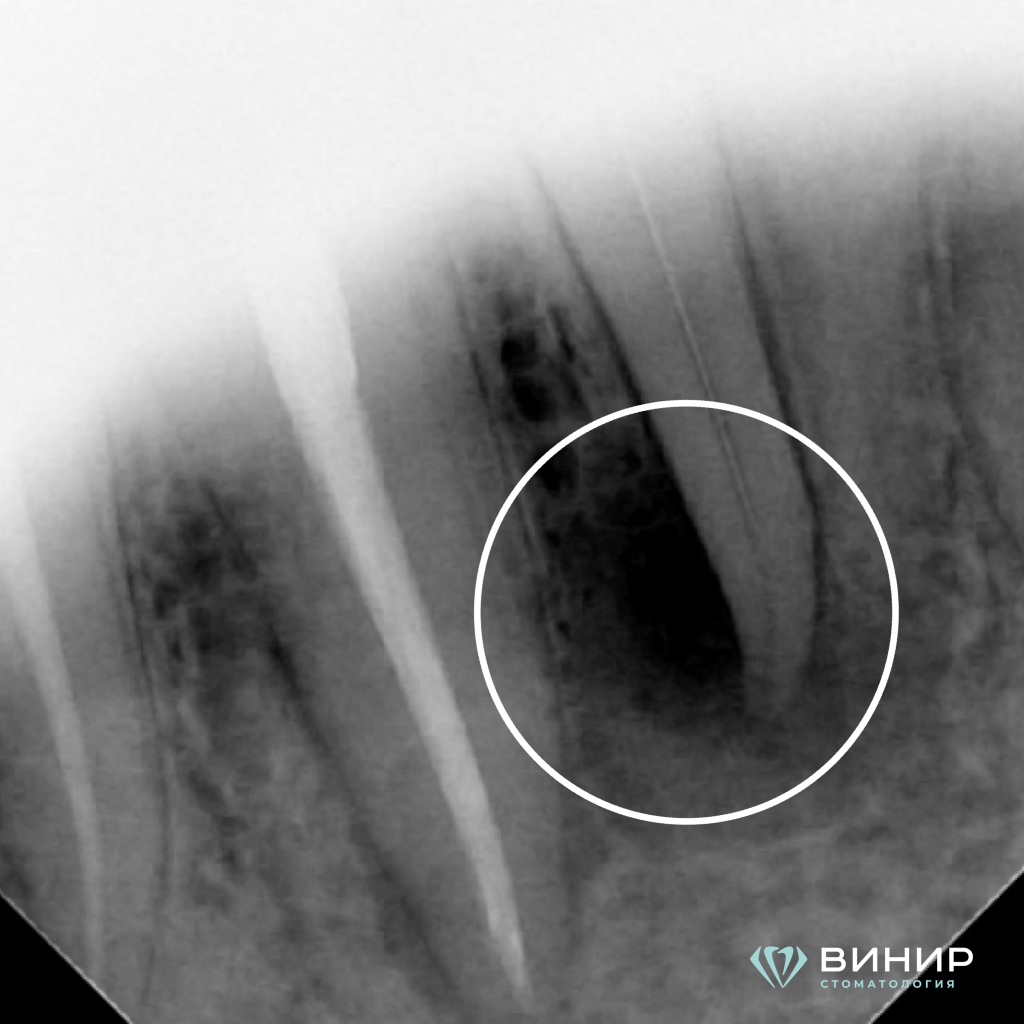

Обратная связь с пациентом спустя сутки после лечения: "Боль прошла, общее состояние улучшилось". Лечение закончено в 2023 году, динамическое наблюдение спустя 2 года (рентген) показало полное заживление очага воспаления в области корня 4.2 зуба.

4. Заживление

4 пункт.PNG